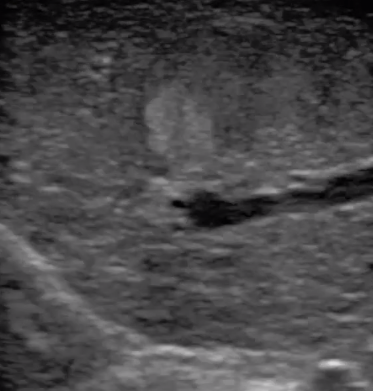

3  腹腔鏡超聲探頭

腹腔鏡超聲是超聲技術(shù)和腹腔鏡技術(shù)的融合,腹腔鏡超聲降低了對超聲探測深度的要求。由微小切口進(jìn)入手術(shù)部位,多角度彎曲可選擇,降低手術(shù)難度及風(fēng)險;與受檢組織器官直接接觸,有效避免氣體干擾。

應(yīng)用科室:麻醉科、手術(shù)室、普外科、泌尿外科、婦產(chǎn)科、腫瘤科、介入科等

腹腔鏡下 肝臟占位